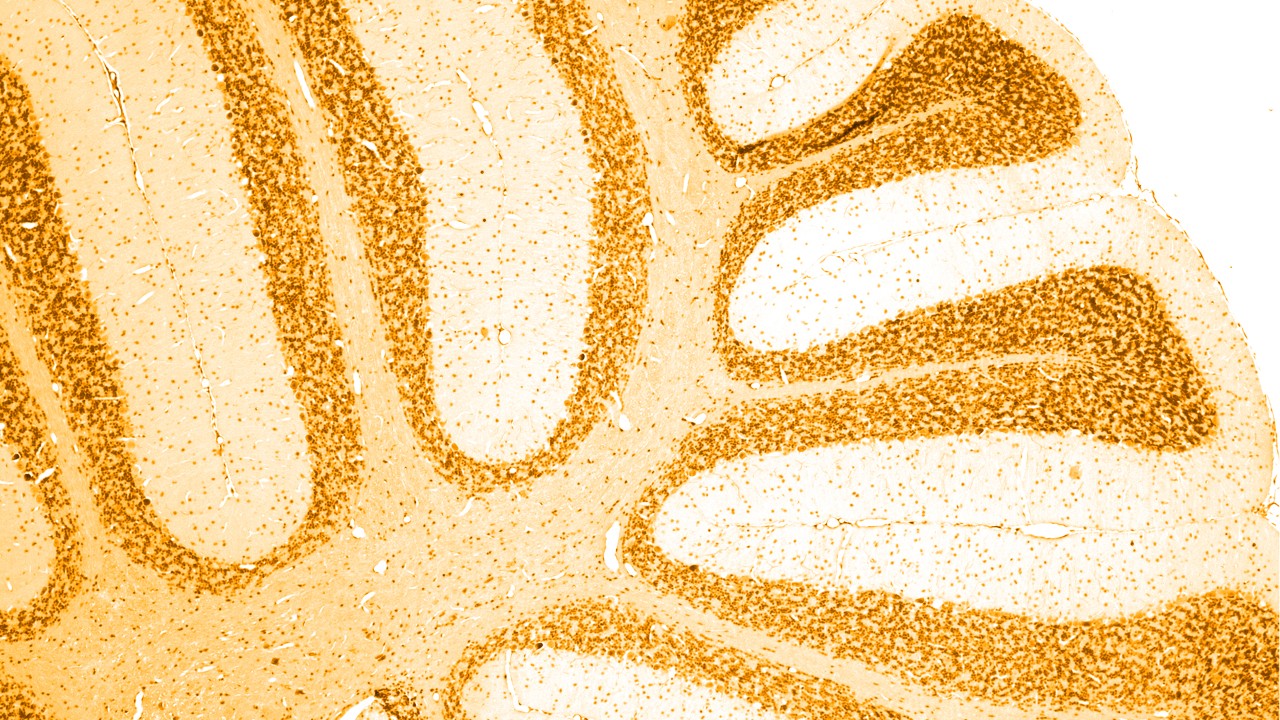

Transtornos neurológicos são doenças do sistema nervoso central e periférico. Em outras palavras, o cérebro, a medula espinhal, os nervos e os músculos que regulam e coordenam as atividades corporais.

Existem várias causas diferentes de demência, das quais a mais comum é a doença de Alzheimer, ligada ao acúmulo de ‘placas amiloides’ e ‘emaranhados tau’ anormais no cérebro. Outros determinados tipos de demência também têm um acúmulo anormal de proteína tau no cérebro; como grupo, esses são denominados ‘taupatias’.